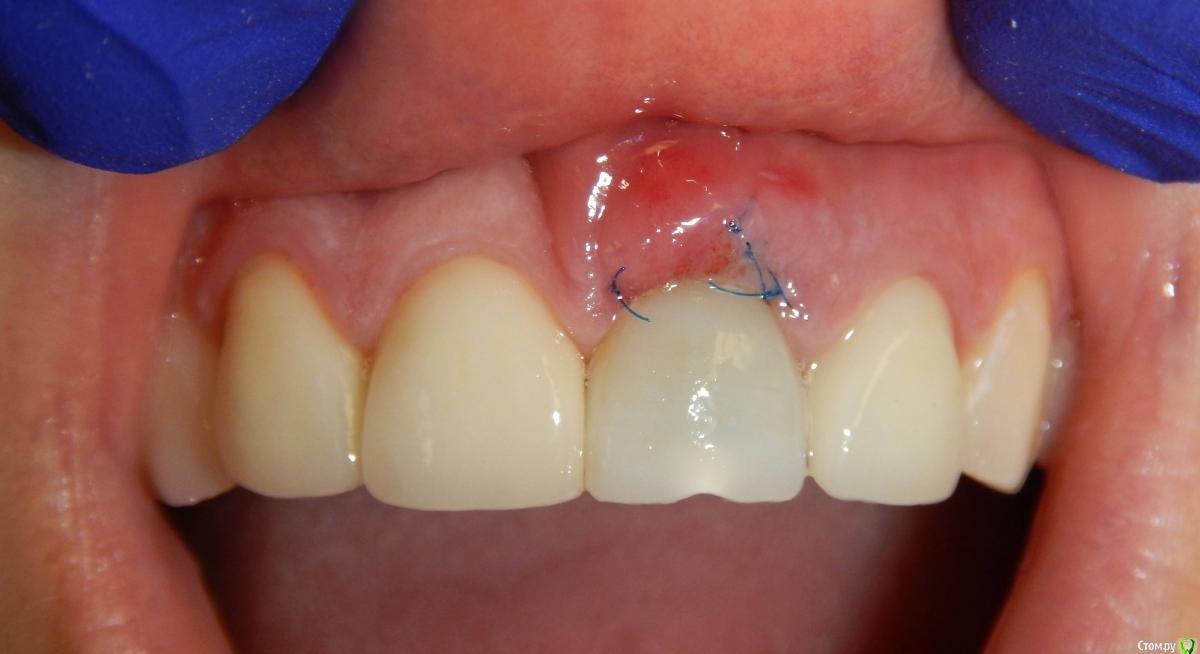

Astronaft Опубликовано 29 января, 2021 Поделиться Опубликовано 29 января, 2021 Я в похожей ситуации взял 4.5мм диаметр, БиоОсс и СТ трансплантат.AnyRidge тот который имеет сердцевину 3.5мм и глубокую агрессивную резьбу - очень хорошо врезается, риск лизиса кости меньше за счет места между витками. 2 Ссылка на комментарий

almaz7888 Опубликовано 31 января, 2021 Автор Поделиться Опубликовано 31 января, 2021 Я в похожей ситуации взял 4.5мм диаметр, БиоОсс и СТ трансплантат.AnyRidge тот который имеет сердцевину 3.5мм и глубокую агрессивную резьбу - очень хорошо врезается, риск лизиса кости меньше за счет места между витками.Спасибо за совет. Такой имплант по лунке лучше встанет, постараюсь взять больший диаметр, чем предполагал ) Ссылка на комментарий

almaz7888 Опубликовано 31 января, 2021 Автор Поделиться Опубликовано 31 января, 2021 А что с зубом, простите? За что ему такой приговор?Добрый вечер! По 2.1 зубу: пациент пришел ко мне на его удаление, подвижность II степени, карман 6 мм, гранулема и костный дефект по апексу, поэтому считаю, что РВК с шинированием фронта не совсем здесь приемлемы. Ссылка на комментарий